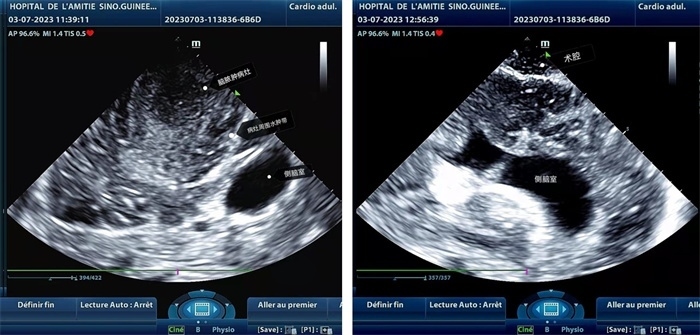

手術(shù)中,張國(guó)濱在超聲科顧秀娟的幫助下,運(yùn)用顱腦術(shù)中超聲技術(shù),通過(guò)將一次性保護(hù)套的超聲探頭置于腦組織表面,實(shí)時(shí)觀察病變的位置和形態(tài),進(jìn)一步確認(rèn)最佳手術(shù)路徑。術(shù)中超聲顯示,病變位于左額頂葉,大小約為4x4x3cm,邊界清晰,呈囊實(shí)性,周邊腦組織水腫明顯。最終,病灶順利切除,診斷為腦膿腫,并通過(guò)超聲檢測(cè)確認(rèn)術(shù)腔無(wú)病變殘留、無(wú)出血,為患者術(shù)后恢復(fù)提供了良好的保障。

左圖顯示術(shù)中超聲見(jiàn)囊實(shí)性病變,大小約為4x4x3cm,病灶周?chē)X組織水腫明顯;右圖為病灶切除后,術(shù)中超聲示術(shù)腔無(wú)病變殘留

左圖顯示術(shù)中超聲見(jiàn)囊實(shí)性病變,大小約為4x4x3cm,病灶周?chē)X組織水腫明顯;右圖為病灶切除后,術(shù)中超聲示術(shù)腔無(wú)病變殘留。中國(guó)第二十九批援幾內(nèi)亞醫(yī)療隊(duì)供圖